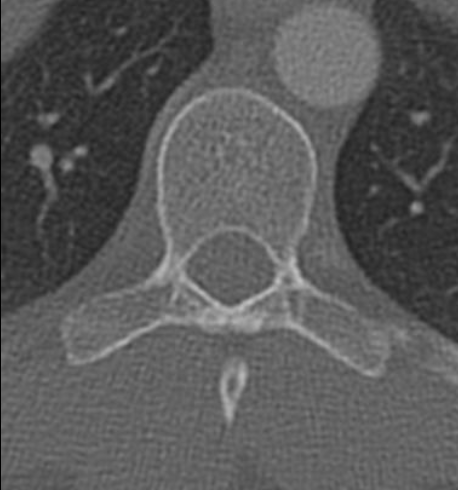

分叉棘突

Bifid Spinous process

前结节

Anterior tubercle

后结节

Posterior tubercle

椎弓根

Pedicle

椎动脉

Vertebral artery

气管

Trachea

胸锁乳突肌

Sternocleidomastoid

颈内静脉

Jugular vein

颈动脉

Carotid artery